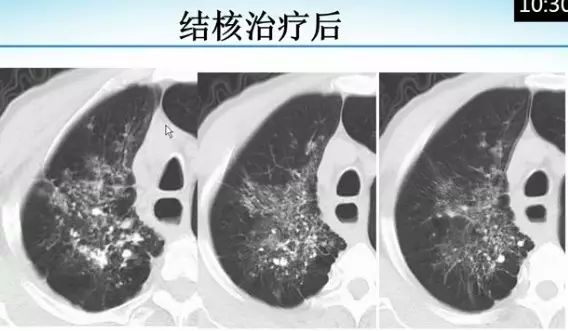

肺内“烟花征”,为活动性肺结核的CT表现之一。是结核经支气管播散并由多发小叶中央结节堆积而成,形态特征似烟花在空中散开。病理基础为细支气管及肺泡内干酪坏死性肉芽肿。

下文为解放军总医院放射诊断科赵绍宏教授课件分享,希望同行朋友们下次遇到类似病例,能够正确诊断。再次感谢赵教授的精彩讲解。